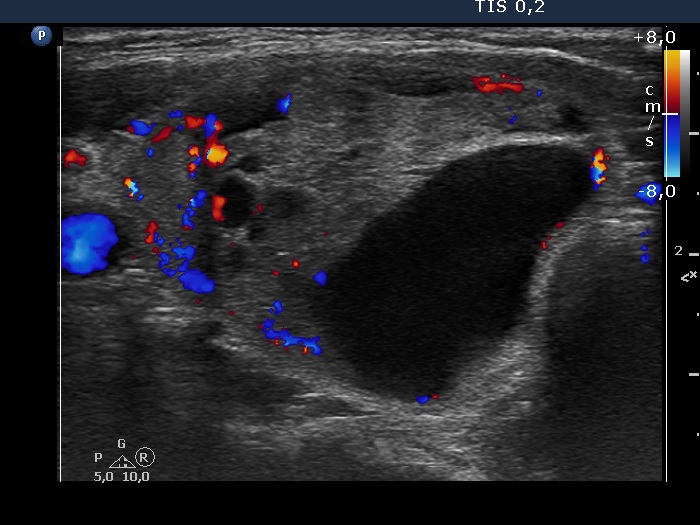

The composition of the nodule - case 1295 (ultrasonographic picture 6)

Right lobe, longitudinal scan

Lower part of the right lobe, transverse scan, color Doppler mode. The lesion presents intranodular blood flow.